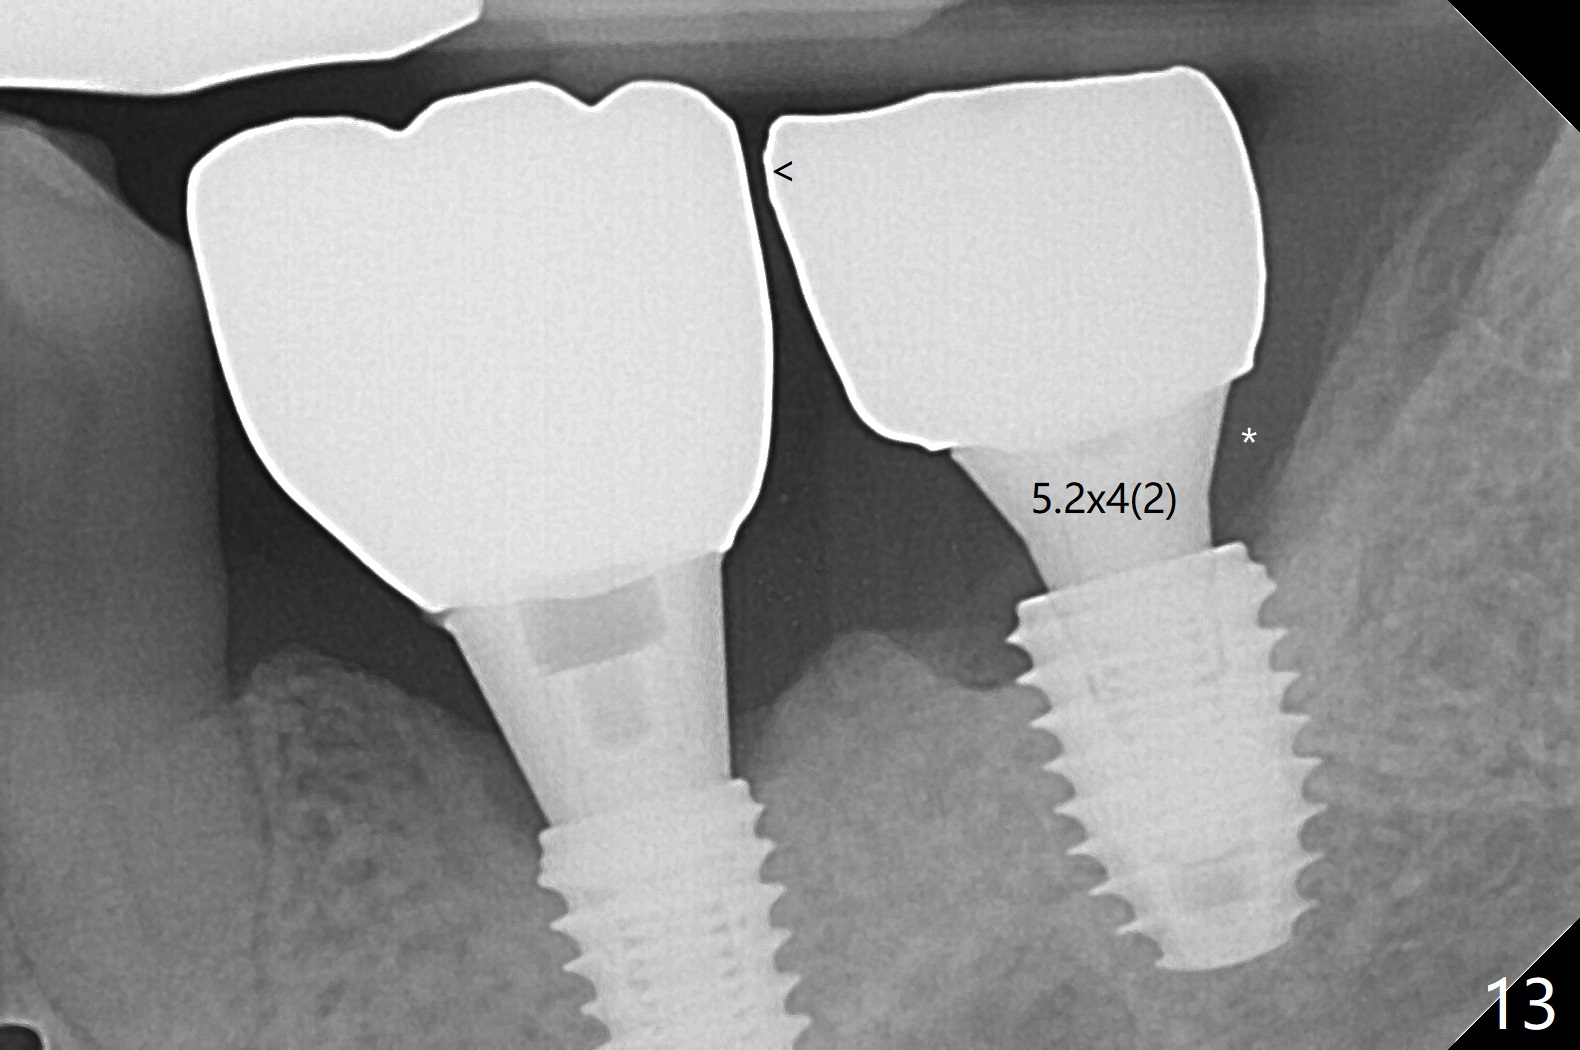

The implants at #12 and 14 are placed 1 month later (Fig.4). The 4 implants have impression (Fig.5,6) and cementation (Fig.7-9) at the same time. Although the upper FPD is able to be removed after cementation in the mouth (Fig.7), the abutment screw cannot be tightened >20 Ncm (Fig.8). The tooth #15 is tender early after crown/FPD cementation and needs occlusal adjustment twice. The crown of #18 dislodges eight months post cementation (Fig.11 taken after recementation). There is no bone loss at #13 and 15 (Fig.10), while the bone density increases around the implants at #18 and 19 eight months post cementation (Fig.11). The abutment screw at #18 become loose 1.5 years post cementation; after proximal surface trimming twice (<), the abutment remains incompletely seated (Fig.12,13). With suspicion of soft tissue block (Fig.13 *), a small abutment with longer cuff is completely seated (Fig.14).